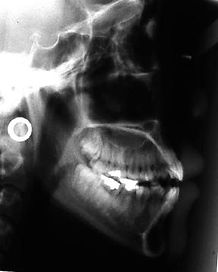

Adult - Openbite

Patient 1 Details

Patient 1